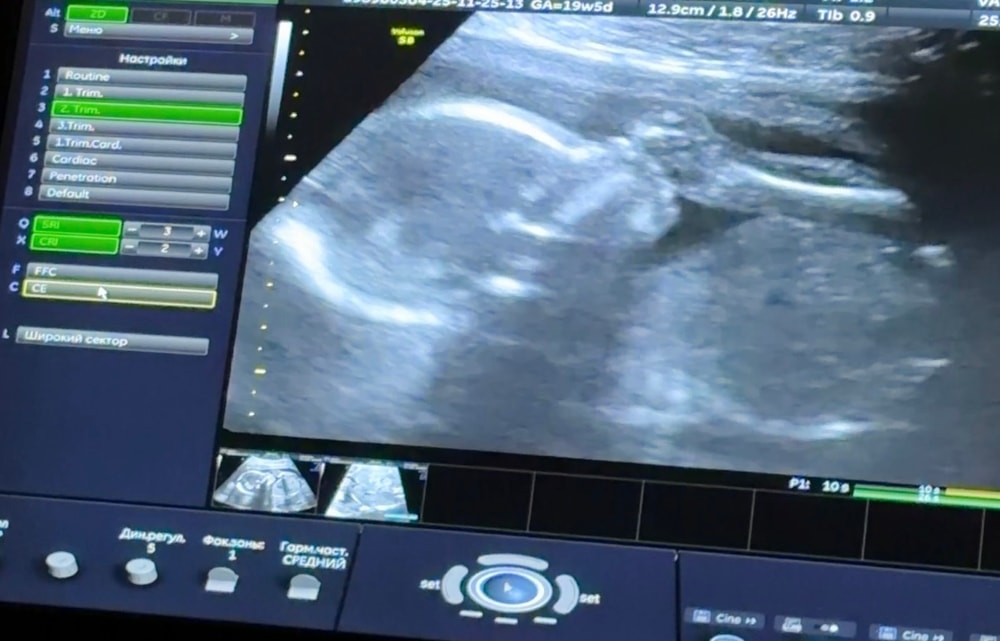

СкринингСегодня 19+5, по узи срок такой же, никаких отклонений нет, и дама весит уже приблизительно 320 гр - я думала исходя из таблиц разных, что на таком сроке 200-250 обычный вес, а тут прям 320😂

Вот тут видно как у нее коленочка у рта, жаль нельзя видео прикрепить как она ее сосёт😅